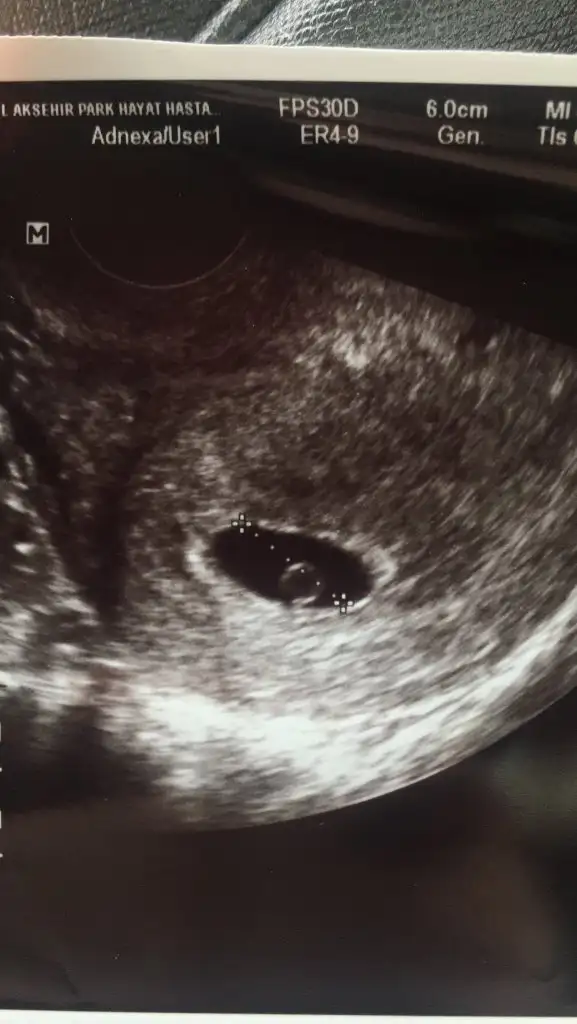

İlk koyduğum ultrason vajinal 5 haftalık, ikincisi görüntü kalitesi daha düşük olan karından 6 haftalık 🥰

• 747FCF6B-325E-4BF7-B5DA-5C3BB6168B83.webp

747FCF6B-325E-4BF7-B5DA-5C3BB6168B83.webp

28,1 KB · Görüntüleme: 278

• 39A6A9E6-5DA9-4813-B2FE-70C636DF5AA5.webp

39A6A9E6-5DA9-4813-B2FE-70C636DF5AA5.webp

18,7 KB · Görüntüleme: 263